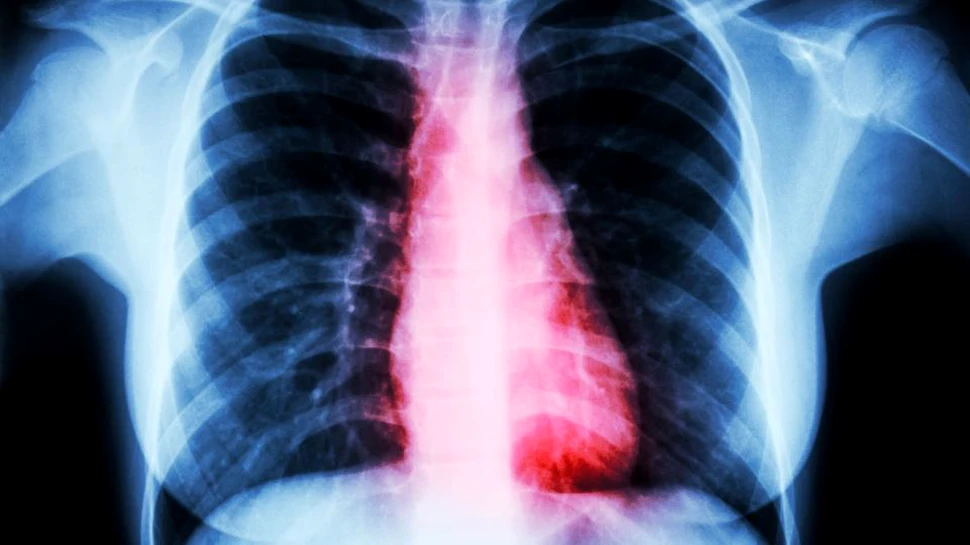

Cercetările au reuşit să demonstreze că pe măsură ce sănătatea cardiovasculară se înrăutăţeşte, exact acelaşi lucru se întâmplă şi cu memoria.

Într-unul dintre cele mai ample studii de acest tip realizate până în prezent, cercetătorii au studiat un grup de aproape 8.000 de persoane din Marea Britanie. Participanţii au avut o medie de vârstă de peste 49 de ani şi starea lor de sănătate a fost urmărită din 2002 până în 2017.

Toţi participanţii aflaţi în studiu au fost relativ sănătoşi la începutul cercetării (atât inima, cât şi creierul erau în condiţii bune de funcţionare). Persoanele cu antecedente de accident vascular cerebral, infarct miocardic, angină, demenţă sau boala Alzheimer au fost excluse.

Ulterior, după 15 ani de urmărire intensivă, aproape 6% dintre participanti suferiseră un atac de cord sau de angină (dureri toracice), potrivit unei echipe conduse de Wuxiang Xie, cercetător la Colegiul Imperial al Şcolii de Sănătate Publică din Londra.

Cercetătorii au descoperit că toţi aceşti participanţi au prezentat şi o scădere mai rapidă a funcţiilor mintale, concomitent cu tulburările cardiace.

Pacienţii care au suferit de angină pectorală au manifestat şi o scădere semnificativă a testelor de „orientare temporală”, nefiind capabili să menţioneze cu precizie data curentă, ziua săptămânii şi per total perioada temporală în care se află.